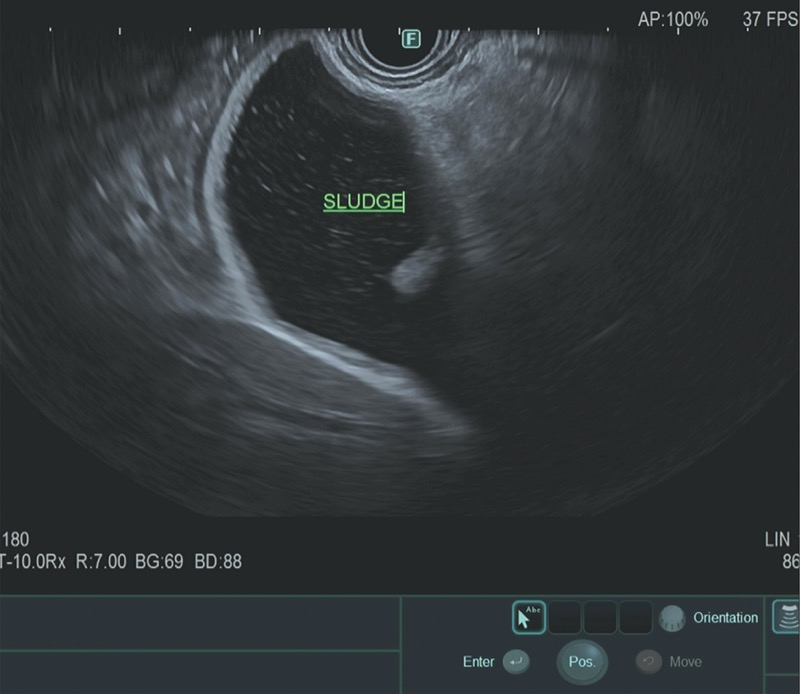

Occult biliary disease has been implicated as a common cause of IAP, with the mechanism being transient obstruction at the ampulla of Vater. Microlithiasis (stones <3 mm in diameter) and biliary sludge—a suspension of crystals (cholesterol monohydrate, calcium bilirubinate, or calcium carbonate), mucin, glycoproteins, cellular debris, and proteinaceous material within bile—can be found within the gallbladder or bile ducts and may be missed by standard imaging. Prospective studies have found that approximately one-fifth to three-fourths of patients with presumed IAP have sludge or stones in the gallbladder, 34,35 with diagnosis based on microscopic examination of bile for crystals and usually confirmed on evaluation of the resected gallbladder or follow-up gallbladder ultrasound showing gallstones and/or sludge.

In the past, at the time of ERCP, it was recommended that bile be collected from the duodenum or bile duct after gallbladder stimulation with cholecystokinin or by direct cannulation of the gallbladder.36,37 Today, however, ERCP rarely is performed specifically for bile crystal analysis, given the risk for post-ERCP pancreatitis and the high sensitivity of EUS in detecting biliary sludge and microlithiasis (Figures 2 and 3A). Furthermore, TUS technology also has advanced significantly, with improved detection rates.

In a large meta-analysis, EUS was found to have a significant benefit in detecting occult biliary disease compared with MRCP (Figure 3B) in IAP.29 Ardengh et al found gallbladder microlithiasis in 27 of 36 patients with IAP using EUS (75%).38 When compared with the final surgical resection specimen, the sensitivity and specificity for EUS identification of gallbladder microlithiasis were 92.6% and 56%, respectively. The overall EUS accuracy in this study was 83.2%.